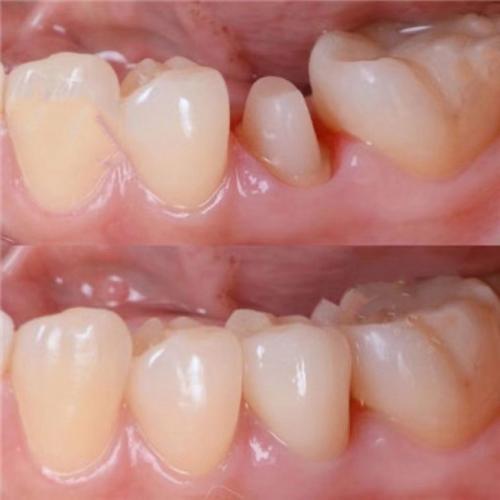

风险:牙冠高度低于5mm(后牙)或6mm(前牙)时,咬合面积不足,咀嚼效率下降,患者可能表现为“咬不动”食物;低牙冠与邻牙间易形成食物嵌塞,长期可能引发邻牙龋坏;前牙区低牙冠还会导致“露龈笑”或“牙冠短小”,影响面部美观。

处理:若修复空间不足导致牙冠过低,需通过正畸压低对颌牙或植骨增加垂直高度;若因设计失误导致,需拆除原牙冠,重新设计牙冠形态,适当延长咬合面,同时通过邻牙牙体预备确保协调性。